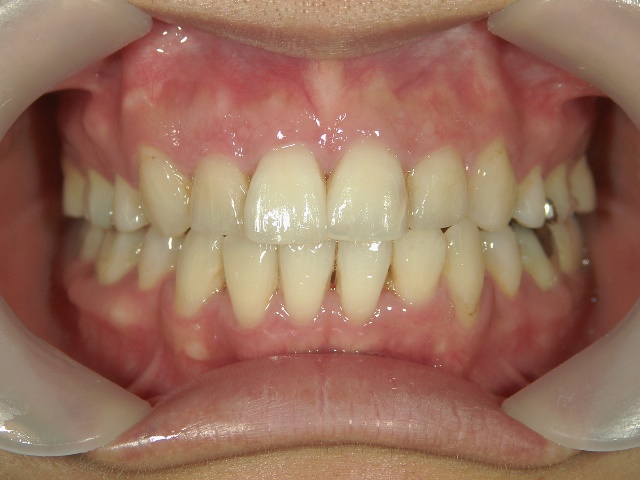

矯正歯科 治療後矯正歯科 全顎ワイヤー矯正 治療後矯正歯科(全顎ワイヤー矯正)治療後

矯正歯科 治療後

no.31_1962_治療後_右.JPGno.31_1962_治療後_正面.JPGno.31_1962_治療後_左.JPG